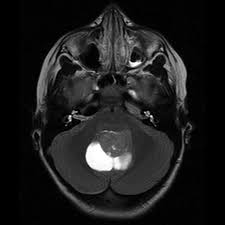

• Meduloblastoma: Son el tipo más común de cáncer cerebral en la infancia, se diagnostica normalmente antes de los 10 años generalmente alrededor de los 5 años. aquí podemos ver una foto de un meduloblastoma.